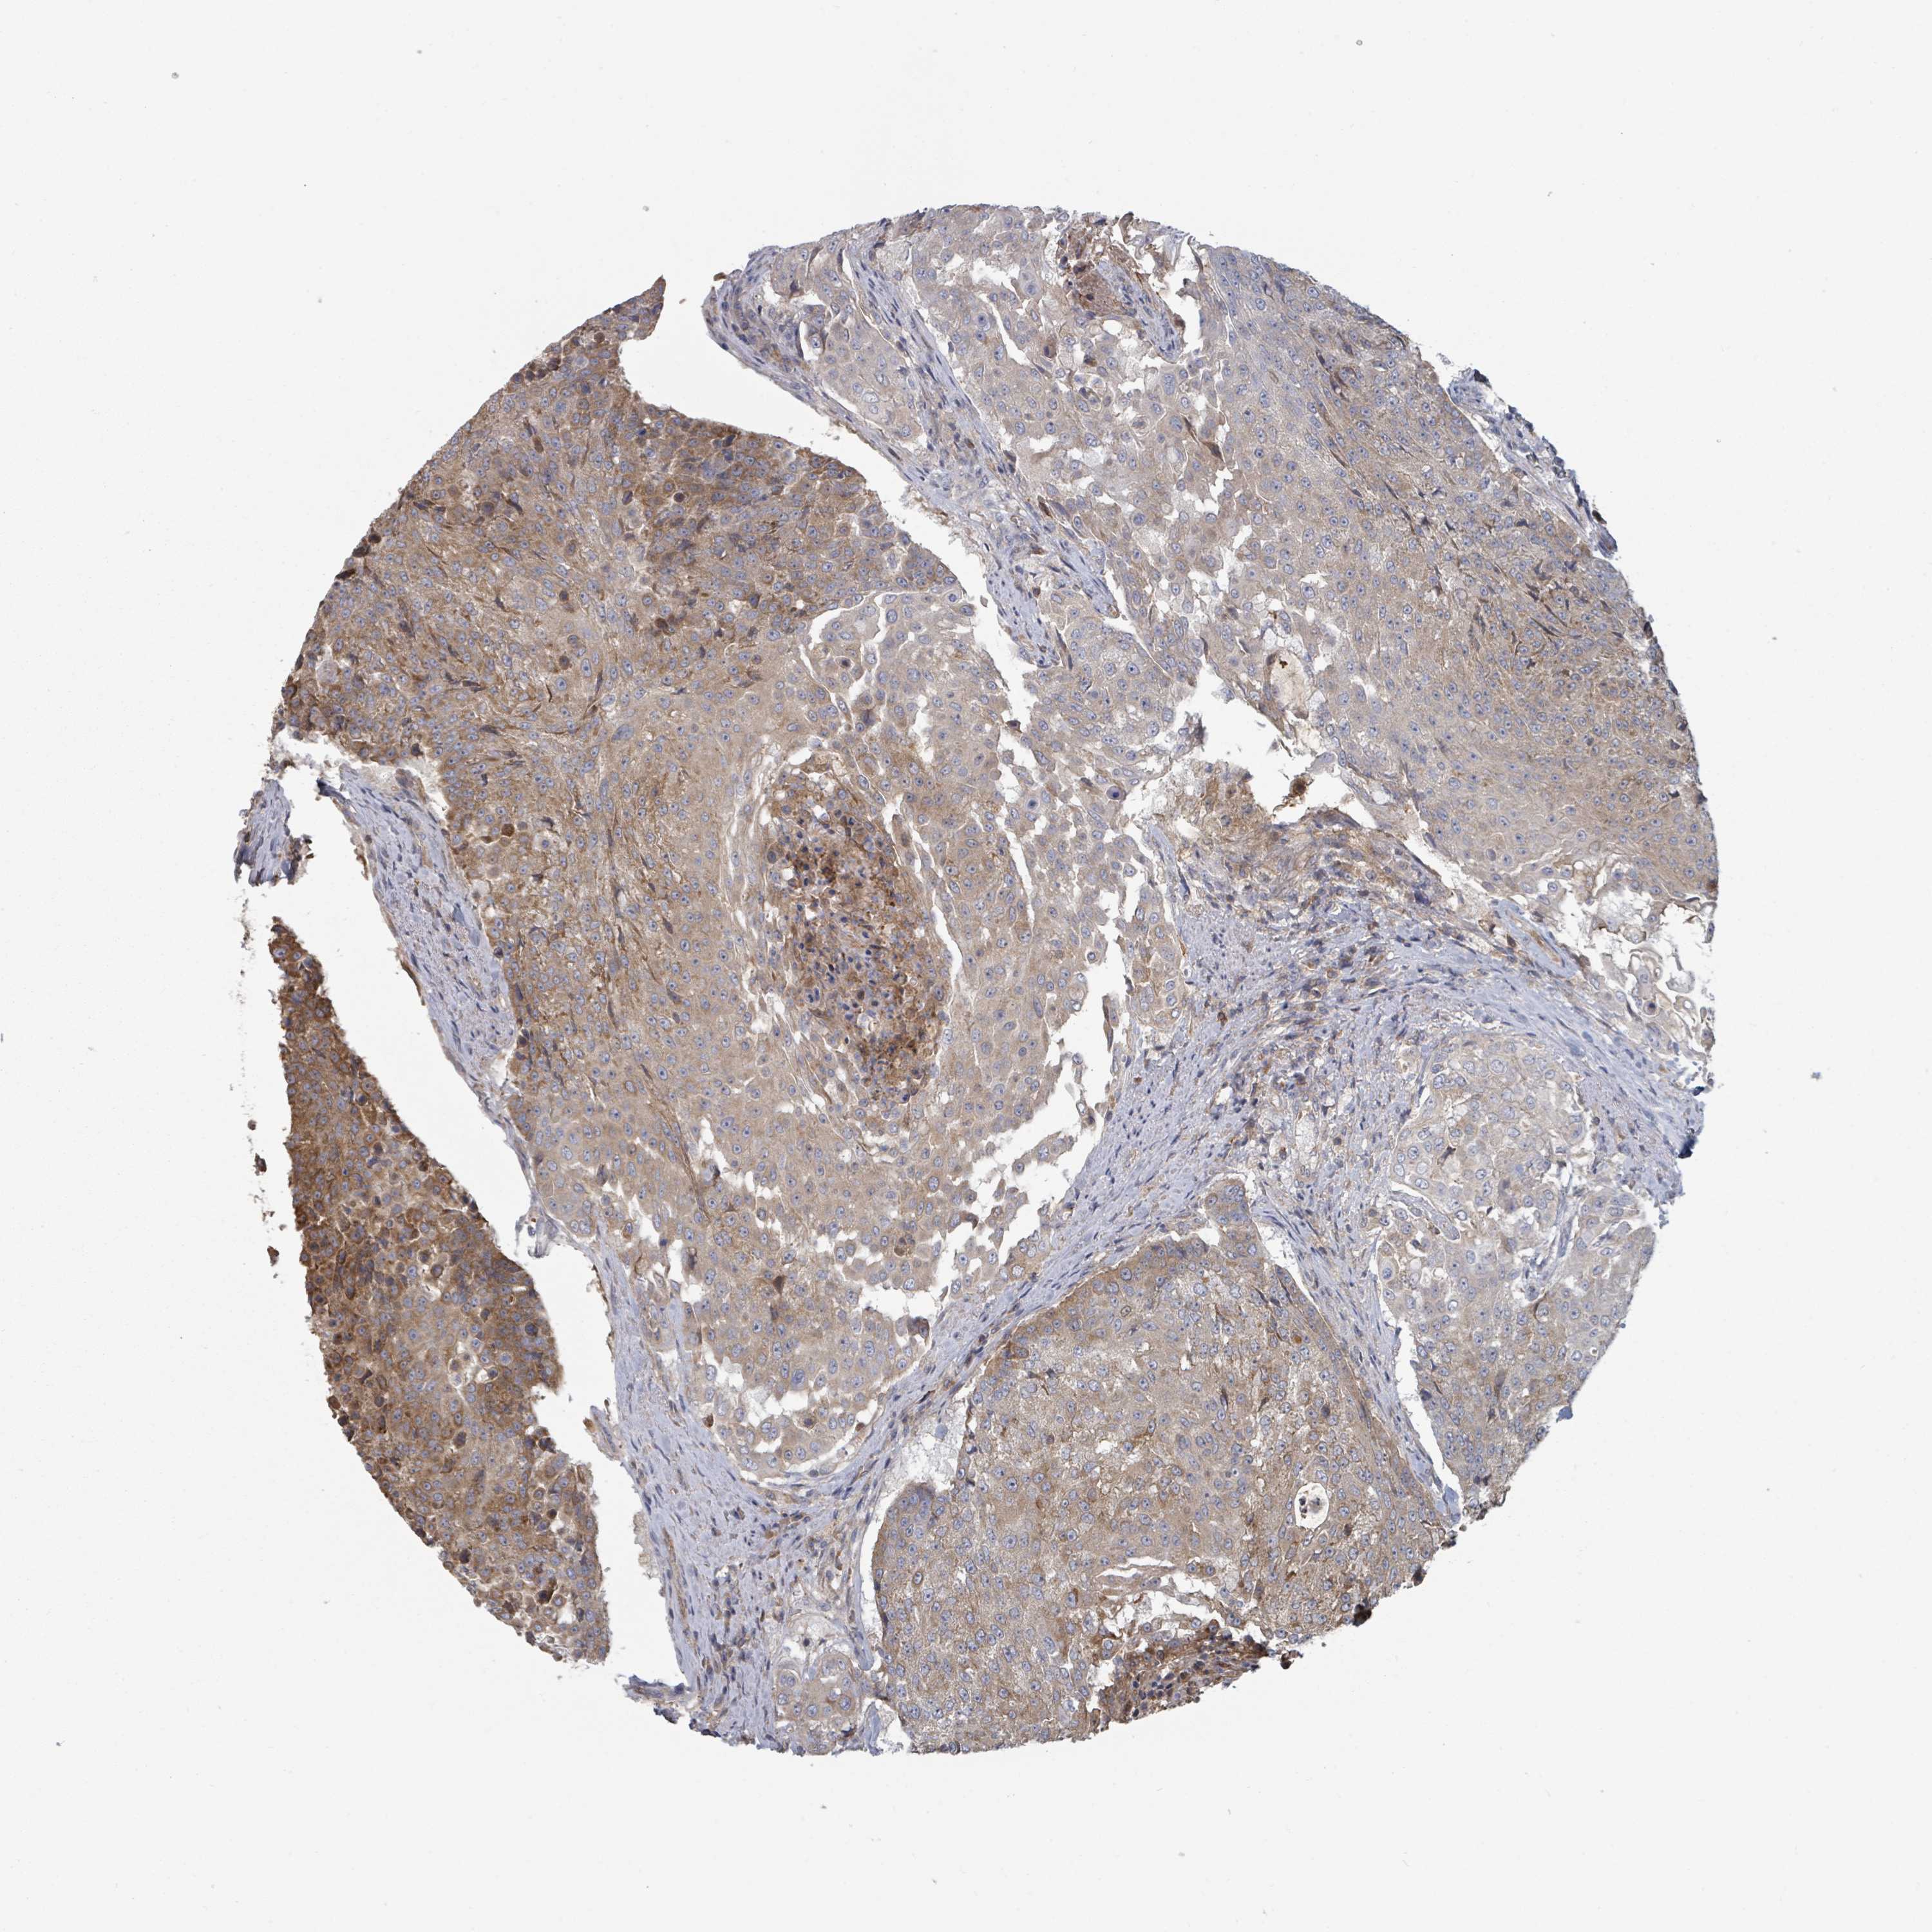

UROTHELIAL CANCER - Protein expressioni

A mouse-over function shows sample information and annotation data. Click on an image to view it in a full screen mode. Samples can be filtered based on level of antibody staining by selecting one or several of the following categories: high, medium, low and not detected. The assay and annotation is described here.

Note that samples used for immunohistochemistry by the Human Protein Atlas do not correspond to samples in the TCGA dataset.

Antibody stainingi

Antibody staining in the annotated cell types in the current human tissue is reported as not detected, low, medium, or high, based on conventional immunohistochemistry profiling in selected tissues. This score is based on the combination of the staining intensity and fraction of stained cells.

Each image is clickable and will lead to virtual microscopy that enables deeper exploration of all samples and also displays staining intensity scores, fraction scores and subcellular localization as well as patient and tissue information for each sample.

Antibody HPA050483

Staining

High

Medium

Low

Not detected

Intensity

Strong

Moderate

Weak

Negative

Quantity

>75%

75%-25%

<25%

None

Location

Nuclear

Cytoplasmic/membranous

Cytoplasmic/membranous,nuclear

Urothelial carcinoma, High grade

Urothelial carcinoma, NOS

Urothelial carcinoma, Low grade